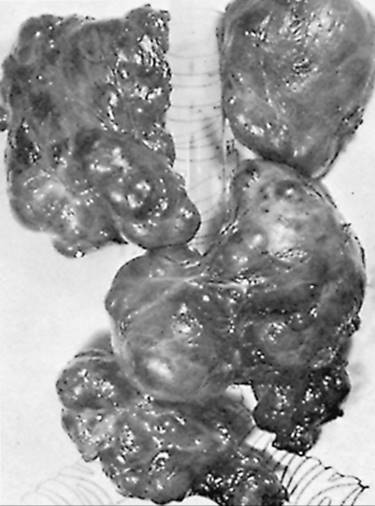

On gross examination, adenomas and nodules are well circumscribed and are often sharply demarcated from the adjacent tissue. They vary in size from about 1 mm in diameter to several centimeters (Fig. 21.4). The typical nodule contains so much colloid that it appears translucent, whereas the classic adenoma is cellular, fleshy, and pale. Hemorrhage, fibrosis, and cystic change may be evident in both nodules and adenomas.

FIGURE 21.4. Nontoxic nodular goiter, largely mediastinal. The trachea and main-stem bronchi are represented diagrammatically.